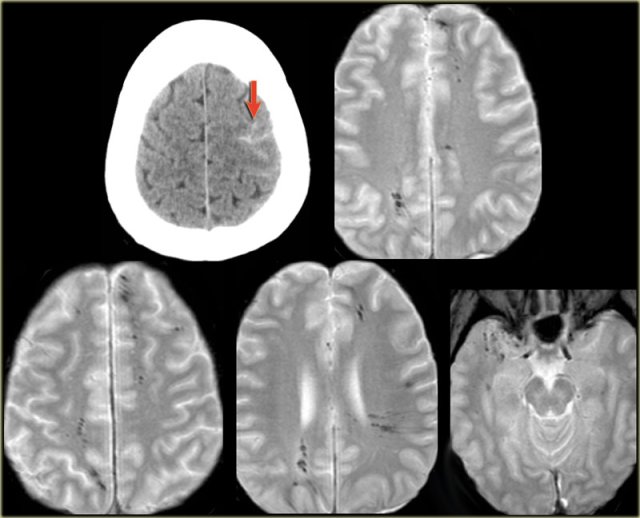

A 46 year old biker presented with seizures after being hit by a car.

CT-image shows only minimal subarachnoidal hemorrhage (arrow).

MRI was performed several weeks after the injury because of a change in personality.

T2*-images show multiple hemosiderin depositions at the interface between grey and white matter, consistent with diffuse axonal injury (DAI).

Notice that the location of the microbleeds is different from the peripheral located CAA-bleeds.